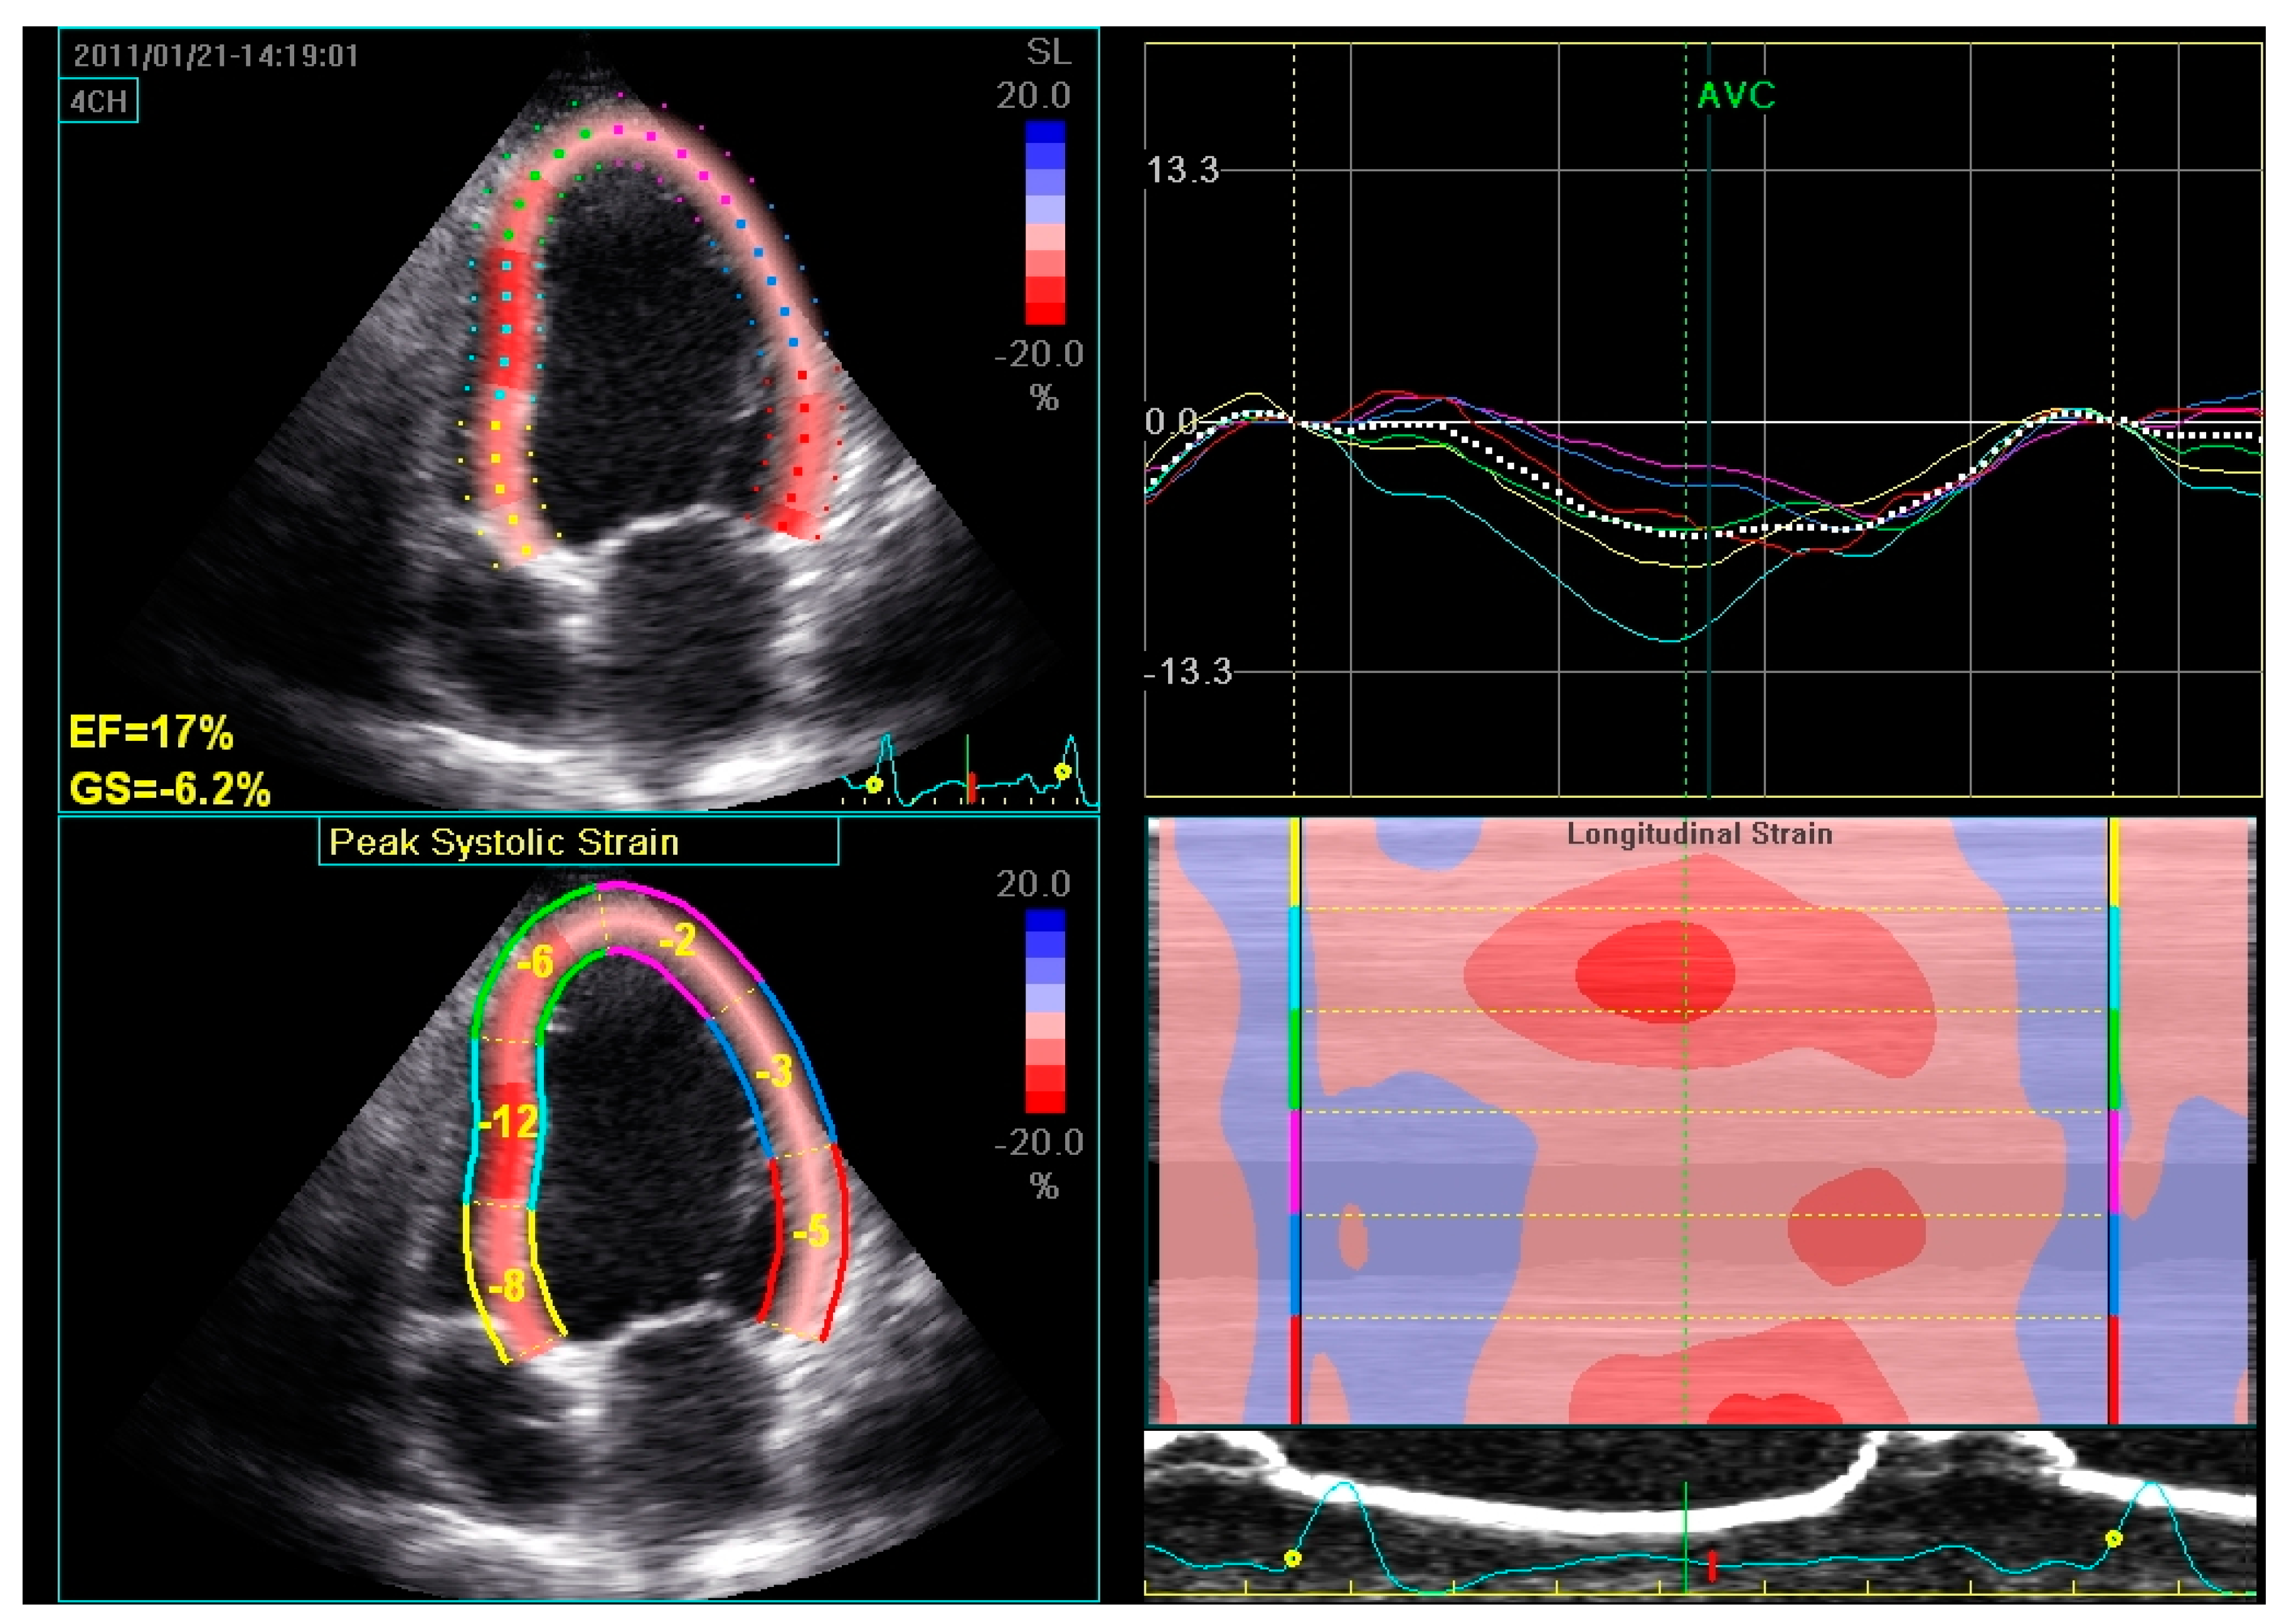

Initially, the decrease in interventricular dyssynchrony was considered the main mechanism underlying CRT response [41]. However, studies have shown that intraventricular, and not interventricular, dyssynchrony is a strong predictor of CRT response [18,42]. Changes in LV dyssynchrony after CRT implantation have been studied by using various echocardiographic methods, including M-mode echocardiography, tissue velocity imaging, strain rate imaging, and 3D echocardiography [5]. Figure 6 shows an example of global longitudinal strain assessed by speckle tracking 2D echocardiography. In a previous study, an improvement in global longitudinal strain, assessed by speckle tracking 2D echocardiography, was observed in CRT recipients at mid-term follow-up both under rest and exercise conditions [43].

Figure 6.

Global longitudinal strain assessed by speckle tracking 2D echocardiography in a patient with dilated cardiomyopathy and severe LV systolic dysfunction. The LV endocardial border is traced by the operator at end-systole and is tracked automatically during the cardiac cycle. Six LV segments, corresponding to the basal, middle, and apical regions of the septum and the lateral wall, are identified by the software. Segmental peak longitudinal strains and global longitudinal strain are assessed automatically and expressed as negative values.